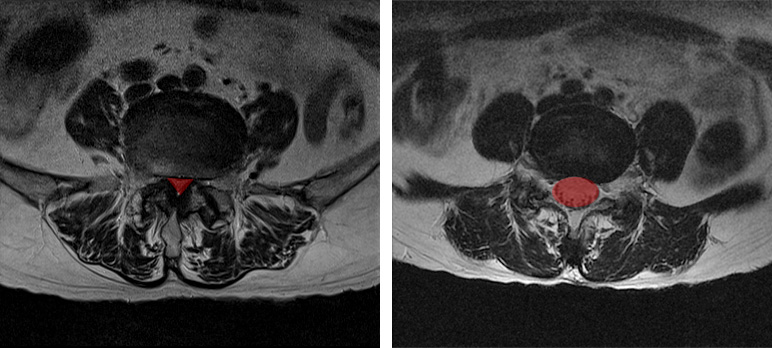

척추관이 좁아지게 되면 MRI로도 많이 좁아진 게 보이며, 반대로 협착증이 아닌 경우에는 MRI 상으로도 공간이 넓습니다. 따라서 단순히 디스크의 높이가 낮아진 것을 보고 이걸 협착이라고 착각하시면 안 됩니다.

그러다 보니 허리를 숙인 상태에서 쇼핑카트를 밀면서 걸으면 통증이 좀 나아지는데, 이 때문에 외국에서는 협착증 환자의 이런 증상을 Shopping Cart Sign이라고 부르기도 합니다. 이 간헐적 신경 파행 증상이 협착증에 동반되는 이유는 협착증은 디스크만의 문제가 아니라 뼈, 후관절, 척추관 내 인대, 디스크 등 모든 척추구조물이 다 퇴행된 상태이기 때문입니다. 그래서 증상이 아주 복합적으로 나오는 것이죠. 따라서 MRI상으로 척추관이 좁아진 것이 보임과 동시에 반드시 간헐적 신경성 파행 증상까지 나타나야만 진정한 의미의 협착증임을 알아두시길 바랍니다.